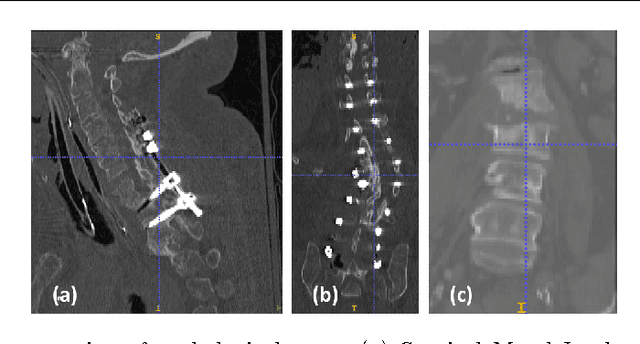

Automatic localization and labeling of vertebra in 3D medical images plays an important role in many clinical tasks, including pathological diagnosis, surgical planning and postoperative assessment. However, the unusual conditions of pathological cases, such as the abnormal spine curvature, bright visual imaging artifacts caused by metal implants, and the limited field of view, increase the difficulties of accurate localization. In this paper, we propose an automatic and fast algorithm to localize and label the vertebra centroids in 3D CT volumes. First, we deploy a deep image-to-image network (DI2IN) to initialize vertebra locations, employing the convolutional encoder-decoder architecture together with multi-level feature concatenation and deep supervision. Next, the centroid probability maps from DI2IN are iteratively evolved with the message passing schemes based on the mutual relation of vertebra centroids. Finally, the localization results are refined with sparsity regularization. The proposed method is evaluated on a public dataset of 302 spine CT volumes with various pathologies. Our method outperforms other state-of-the-art methods in terms of localization accuracy. The run time is around 3 seconds on average per case. To further boost the performance, we retrain the DI2IN on additional 1000+ 3D CT volumes from different patients. To the best of our knowledge, this is the first time more than 1000 3D CT volumes with expert annotation are adopted in experiments for the anatomic landmark detection tasks. Our experimental results show that training with such a large dataset significantly improves the performance and the overall identification rate, for the first time by our knowledge, reaches 90 %.